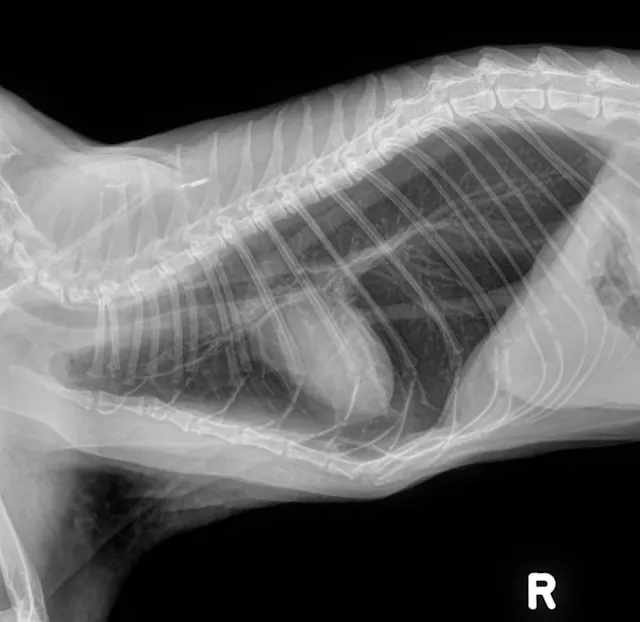

• Thoracic radiographs (3 views): Initial interpretation by overnight doctors was significant elevation of the cardiac silhouette from the sternum (moderate pneumothorax); diffuse bronchial pattern; moderate to severe subcutaneous emphysema of the left axilla. (See Radiographs)

• Radiologist interpretation of post-thoracocentesis radiographs:  Iatrogenic moderate pneumothorax; condition appeared worse after thoracocentesis than before

The cat initially presented with a fever and lethargy; then developed acute dyspnea while hospitalized. The diagnosis and decision to treat for pneumothorax was an unfortunate misstep. The films taken upon referral are consistent with a bronchial pattern and show evidence of overinflation. Lung tissue is present throughout all lung fields and, although the cardiac silhouette is elevated, this is due to air trapping within the alveoli and not a pneumothorax. In general, a ventrodorsal view is good for confirming the presence of a pneumothorax: there would be black areas where the lung is pulled away from the chest wall as a result of air in the pleural space. In these films, lung tissue can be seen all the way to the edges of the thoracic cavity. As a side note, spontaneous pneumothorax has been reported in asthmatic cats, so it is not out of the realm of possibility.1

Radiographic Interpretation

Pneumothorax was diagnosed here based on the elevation of the heart from the sternum, which can be one of the signs of pneumothorax. However, it is extremely important to look at the entire radiograph.  In these, (see images) the lung fields can be followed to the edge of the chest cavity on both the lateral and ventrodorsal views: there is no air surrounding the lung lobes. Although the heart looks raised, the area ventral to the heart on the lateral images shows a soft tissue opacity (possibly fat), not air. The lungs are hyperinflated, which is consistent with primary lung disease and not a typical sign of pneumothorax.